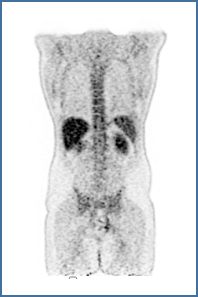

Um das volle Potential neuartiger Bildgebungssysteme auszuschöpfen, arbeiten wir an neuen Bildgebungsmethoden und optimieren Bildgebungsprotokolle gemeinsam mit unseren klinischen Partnern. Diese Bemühungen umfassen neuartige Akquisitionsschemata für z.B. dynamische Ganzkörperbildgebung, Einbeziehung von Bewegungsmanagement und Dosis- und Akquisitionszeitreduktion. Darüber hinaus befassen wir uns mit der Auswertung klinischer Daten und arbeiten an Mitteln zur Standardisierung und Harmonisierung quantitativer Bildgebungsdaten.